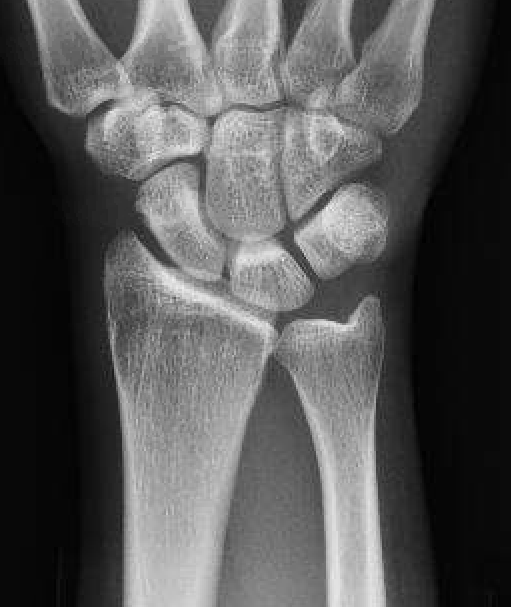

Ulna variance

Supination and pronation alter variance

- varies up to 3 mm with wrist position

- pronation increases ulnar variance

- supination decreases variance

90 / 90 view

- zero rotation view

- neutral supination / pronation

- PA film with wrist in neutral

- elbow 90° / shoulder abducted 90°

Line from lunate fossa and ulna head

- wide variation in population

- mean ulna variance is 1 mm (range 2 - 4)

Ulna neutral

Ulna positive

Ulna negative